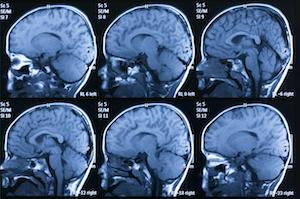

Brain Injury

A Traumatic Brain Injury (TBI) usually results from a violent blow or jolt to the head or a penetrating head injury that disrupts the normal function of the brain. A common mild brain injury is often referred to as a concussion. Brain injuries are often permanent and disabling.

According to the ByYourSide.org, a TBI can cause a wide range of functional changes—short or long-term—affecting thinking, language, learning, emotions, behavior and/or sensation. Memory loss, difficulty with judgment and recognition of limitations, anxiety and/or depression, loss of social networking, feelings of isolation, slowness or difficulty with speech, decreased physical coordination, decreased anger management, decreased safety awareness, and difficulty initiating, planning and completing tasks. All of these significant injuries can be the consequences of TBI. In some instances, TBI’s can cause long-term complications leading to attempted suicide or death.

According to the Centers for Disease Control (CDC) each year an estimated 1.5 million Americans sustain a TBI. Approximately 138 people die each day from injuries of a Traumatic Brain Injury. That’s more than 50,000 deaths attributed to TBIs. While 230,000 people are hospitalized and do not suffer a life threatening TBI, 80-90,000 do experience long-term disability. While falls are the leading cause of TBI’s, motor vehicle crashes and traffic related accidents result in the largest percentage of TBI deaths.